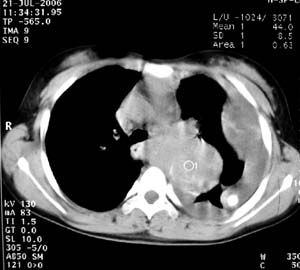

女性,17岁,一年前因股骨病变截肢,现胸憋。

股骨下段针状瘤骨垂直于骨皮质向外生长.并见软组织密度肿块影.骨髓腔密度增高.考虑股骨下段成骨肉瘤.胸膜及左肺转移瘤.

左肺巨大肿块,内散在斑点状高密度骨化影,右肺见多发结节灶,双侧胸膜局限性增厚。有骨肉瘤病史,支持骨肉瘤手术后转移。